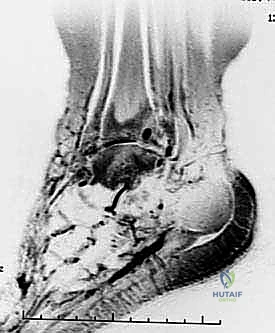

تبدأ رحلة العلاج مع الأستاذ الدكتور محمد هطيف بتقييم شامل. يتم إجراء فحوصات دموية كاملة، وتخطيط للقلب، والأهم من ذلك: التصوير الطبي المتقدم.

يعتمد الدكتور هطيف على الأشعة السينية (X-rays) والأشعة المقطعية (CT Scans) ثلاثية الأبعاد لبناء خريطة دقيقة للتشوهات العظمية وتحديد حجم ومسار المسمار النخاعي المناسب لكل مريض بدقة متناهية. يتم مناقشة كل هذه التفاصيل بشفافية تامة مع المريض.

يتم عمل شق صغير أسفل الكعب. يتم إدخال سلك توجيهي، يتبعه إدخال المسمار النخاعي القوي المصنوع من التيتانيوم. يخترق المسمار عظمة الكعب، ثم يمر عبر عظمة الكاحل، ليستقر أخيراً داخل القناة النخاعية لعظمة الساق.

5. التثبيت بالبراغي القفلية (Locking Screws)